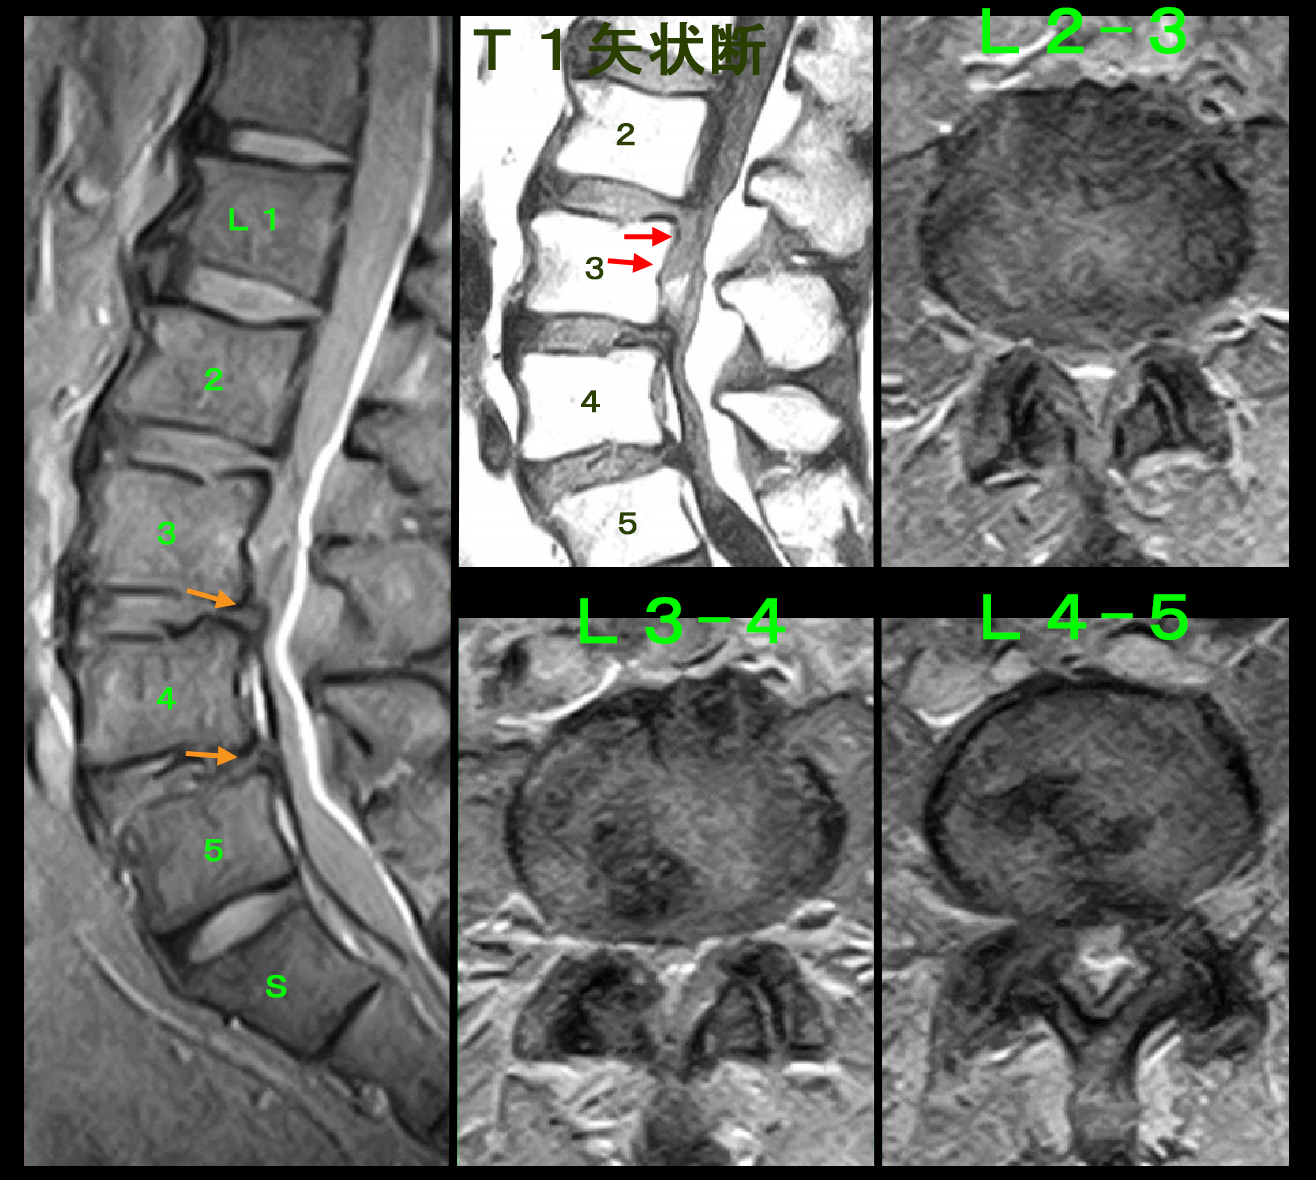

今回のMRI検査ではおおむね前回と変化がない印象ですが、右の4分解の左上のT1矢状断の画像でL2-3の椎間板がグレーに下方に垂れ下がるように出っ張っています。

令和2年4月のMRI画像との比較ですが、L2-3の椎間板は明らかに悪化しています。これが今回の重度の左坐骨神経痛の原因です。